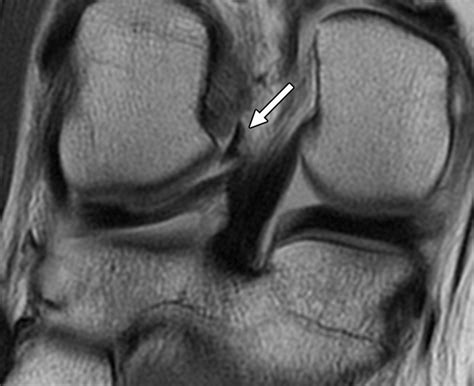

If you suspect an injury to the lateral meniscus, it is essential to consult a healthcare professional. A physical examination typically involves the McMurray test or the Apley compression test to reproduce pain and identify the location of the tear. To confirm the diagnosis and rule out other structural issues, your doctor may request specific imaging.

MRI (Magnetic Resonance Imaging) Provide detailed images of soft tissues to visualize the tear.